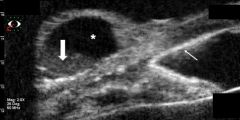

Ultrasound Biomicroscopy

UBM is a high-resolution noninvasive tool of great value in diagnosing anterior chamber cystic lesions. UBM can be used to assess their content (whether hypodense or hyperreflective),[18] differentiating them from solid lesions.[19] Through UBM examination, it is possible to define whether the cyst has primary or secondary origin. Consuelo et al. observed that secondary implantation cysts have relatively thick walls and that their content may be hypodense (translucent) with several particles in suspension (probably desquamating epithelial cells [Figure 4]) or arranged in hyperreflective concentric layers corresponding to keratin lamellae. On the other hand, primary cystic lesions were characterized by a thin, highly reflective wall with hypodense content.[20]

Figure 5 shows a conjunctival cyst after vitreoretinal surgery with silicone oil insertion (UBM 50-MHz transducer, immersion technique).

Figure 5A. UBM longitudinal scan demonstrates an elevated, round cystic lesion at the limbal area, filled by hyporeflective content (*) and an inferior deposit of punctiform particles (thick arrow). Note highly reflective deposit at the angle, endothelial line, and iris surface (thin arrow). (Courtesy of Norma Allemann, PhD. Department of Ophthalmology, Federal University of São Paulo, Brazil.)

Figure 5B. UBM cross-section of the cystic lesion, hyporeflective content (*), and an inferior deposit with punctiform particles (thick arrow). The posterior limit with the sclera is easily detected. (Courtesy of Norma Allemann, PhD. Department of Ophthalmology, Federal University of São Paulo, Brazil.)